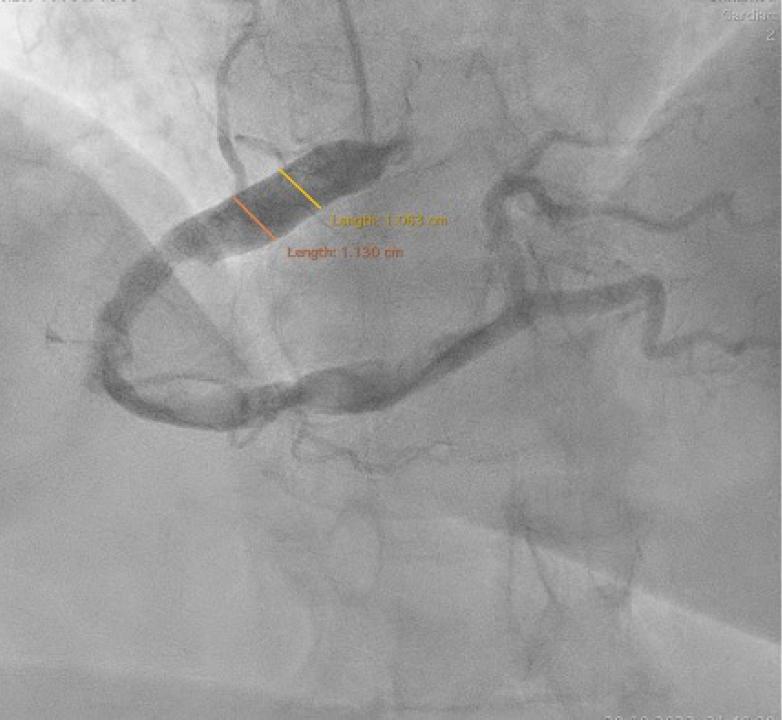

Right radial artery arterial access was obtained. Selective cannulation and injection of contrast medium in the right coronary artery (RCA) discovered a dominant artery, dilated on its entire length (maximum diameter of 11.3 mm in the proximal segment) with high thrombotic burden in the mid and distal segments (Fig. 2).

Left anterior oblique projection of the right coronary artery. Significantly dilated right coronary artery (RCA) on its entire length, seen in left anterior oblique projection. Arrows indicate high quantity of thrombotic material in the mid-distal RCA.